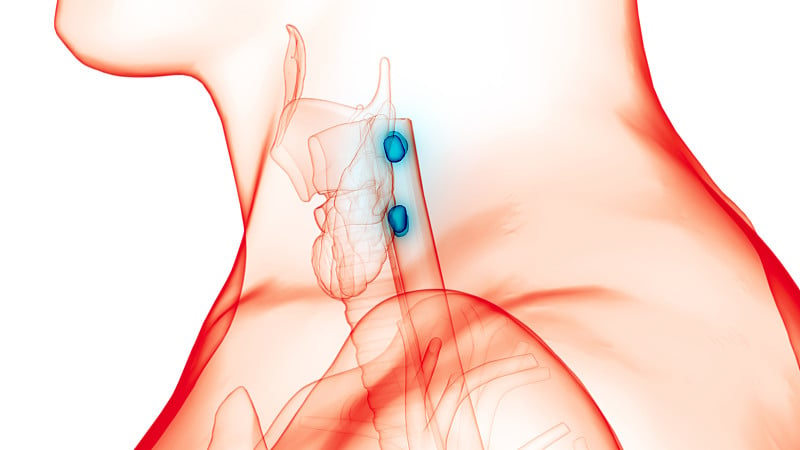

人体腺体甲状腺解剖学详情

人类甲状腺详情

人体腺体甲状腺解剖学详情

人体腺体甲状腺解剖学详情

人体腺体甲状腺解剖学详情

人体腺体甲状腺解剖学详情

人体腺体甲状腺解剖学详情

人体腺体甲状腺解剖学详情

人体腺体甲状腺解剖学详情

人体腺体甲状腺解剖学详情

人体腺体甲状腺解剖学详情

人体腺体甲状腺解剖学详情